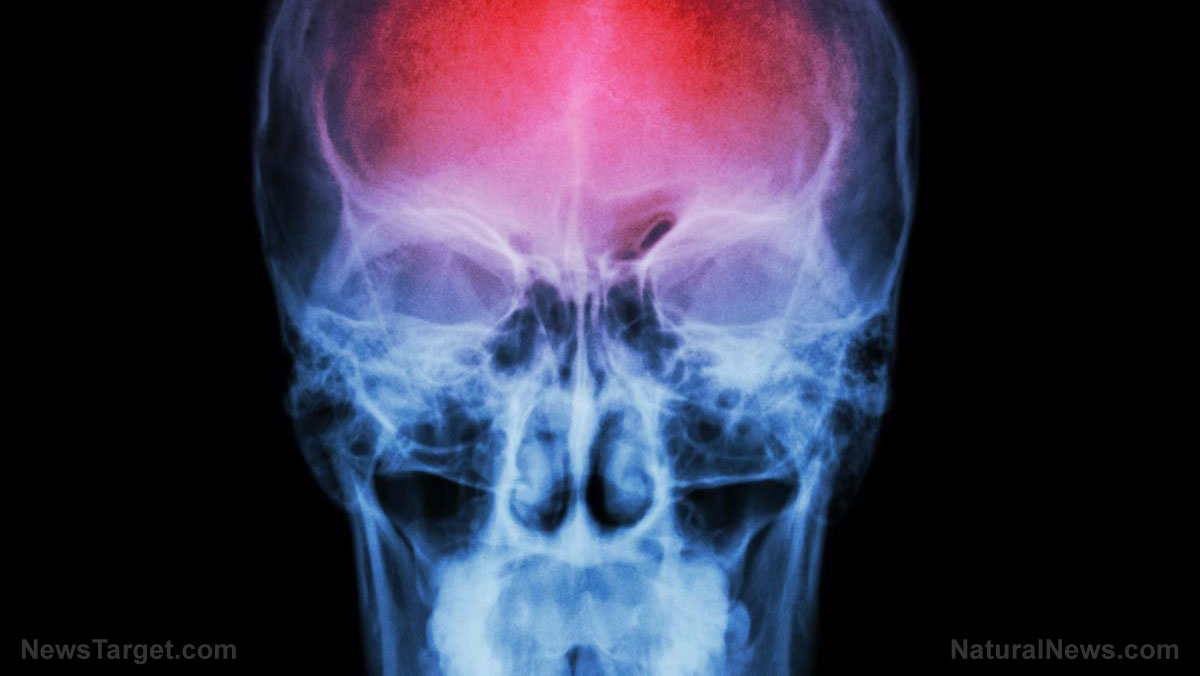

This natural remedy may protect you from brain damage

(Natural News) Stroke is one of the leading causes of death in the U.S. Stroke survivors have a high risk of developing significant brain damage. Although there is a limited number of medications that treat stroke-induced brain damage, scientists have observed that there are plants with neuroprotective compounds that can be developed for this purpose. A team of researchers from The Federal University...